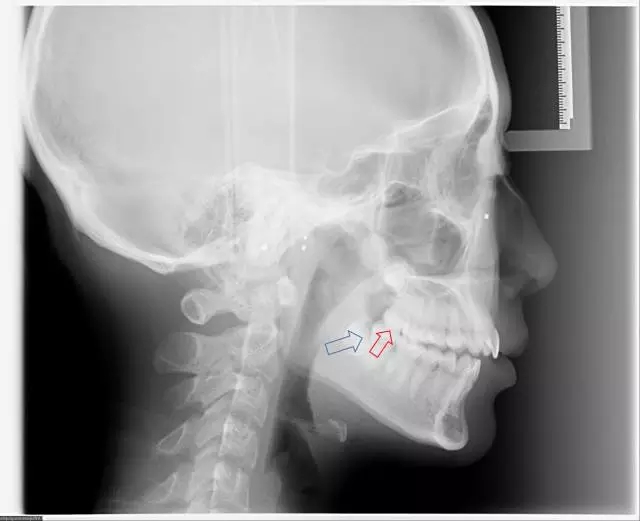

第二,完全埋在骨頭里可以不拔?

完全埋在牙槽骨里的下頜智齒,它本身倒是不出問(wèn)題。但是這些近中或水平阻生的智齒,會(huì)推擠下頜第二磨牙,導(dǎo)致第二磨牙伸長(zhǎng):

然后,第二磨牙造成咬合干擾、早接觸,前牙開(kāi) 牙合…………

甚至髁突吸收:

所以,這種智齒也還是要 拔掉。